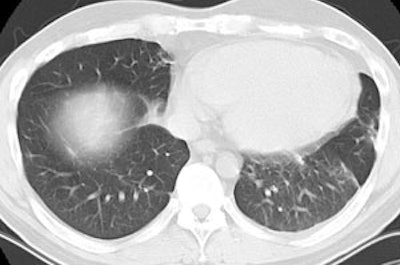

BOOP presenting with pulmonary nodules:

Open lung biopsy confirmed the diagnosis of BOOP. Following institution of therapy with steroids the lung lesions resolved. Click images to enlarge.